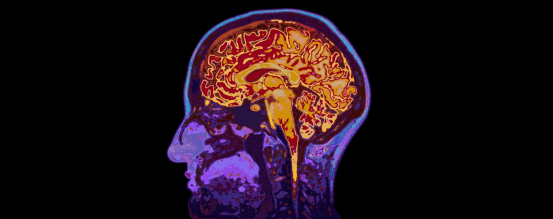

艾滋患者比常人出现中风的机率更高 , 但造成这种情况的原因却未被关注 。 在最近举行的 2021国际艾滋病协会科学会议上 , 一篇学术报告中的数据为探究其原因提供了依据 。

“即使在考虑了传统风险因素和艾滋病毒相关变量后 , 艾滋患者缺血性中风的发生率仍高达 65% , ”研究人员说 , 与神经炎症途径相关的压力可能是原因所在 , 因此他们研究了“压力、与压力相关的大脑区域代谢活动和 18f -氟脱氧葡萄糖 (FDG)-PET[正电子发射断层扫描

动脉炎症之间的关系 , 后者可预测缺血性中风和其他心血管问题 。 ”